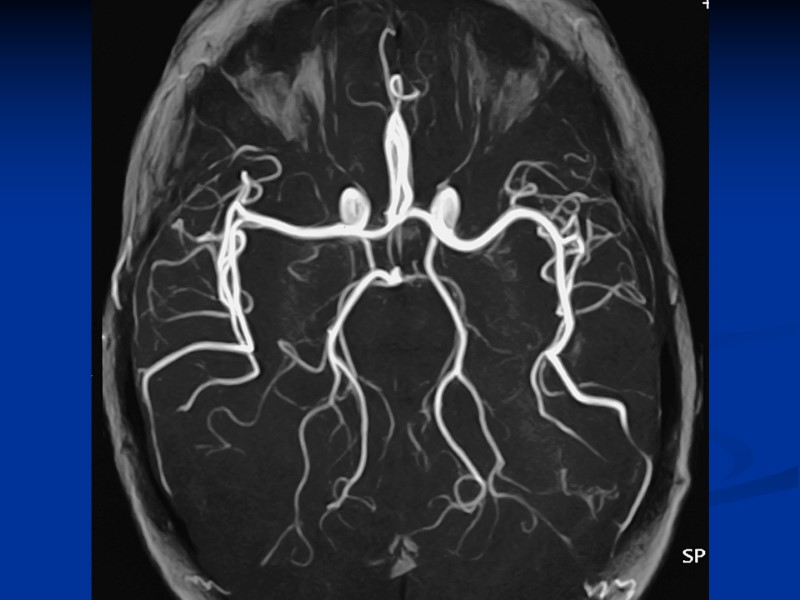

Алгоритм променевого дослідження черепа. 1.Рентгенографія в 2-ох проекціях . Візуалізує стан, величину, форму, контури, структуру кісток черепа. 2. Комп’ютерна томографія, МРТ. Показання: ознаки порушення мозкового кровообігу підвищення внутрішньочерепного тиску загально мозкова і вогнищева неврологічна симптоматика порушення зору, слуху, мови, пам’яті 3. УЗД. дослідження головного мозку у ранньому дитячому віці через тім’ячка вивчення мозкового кровообігу 4. Сцинтиграфія головного мозку для візуалізації пухлини.